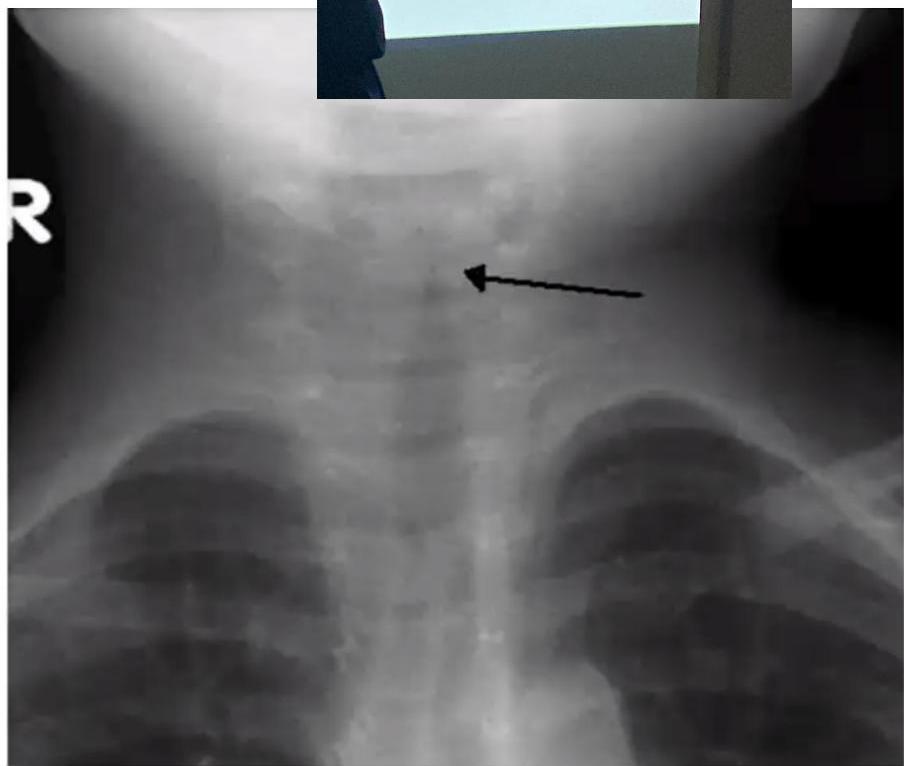

Croup (Laryngotracheobronchitis)

Radiographic Sign: Steeple or pencil sign of the proximal trachea

Signs:

- Inspiratory stridor

- Barking cough

- Hoarseness

Causes:

- Parainfluenza virus type 1

- RSV

- Influenza virus

Management:

- Mild symptoms: Single dose of oral dexamethasone

- Moderate to severe symptoms:

- Supportive care: humidified air or oxygen, intravenous fluids

- Epinephrine

- Dexamethasone

- Surgical intervention if patient doesn’t improve